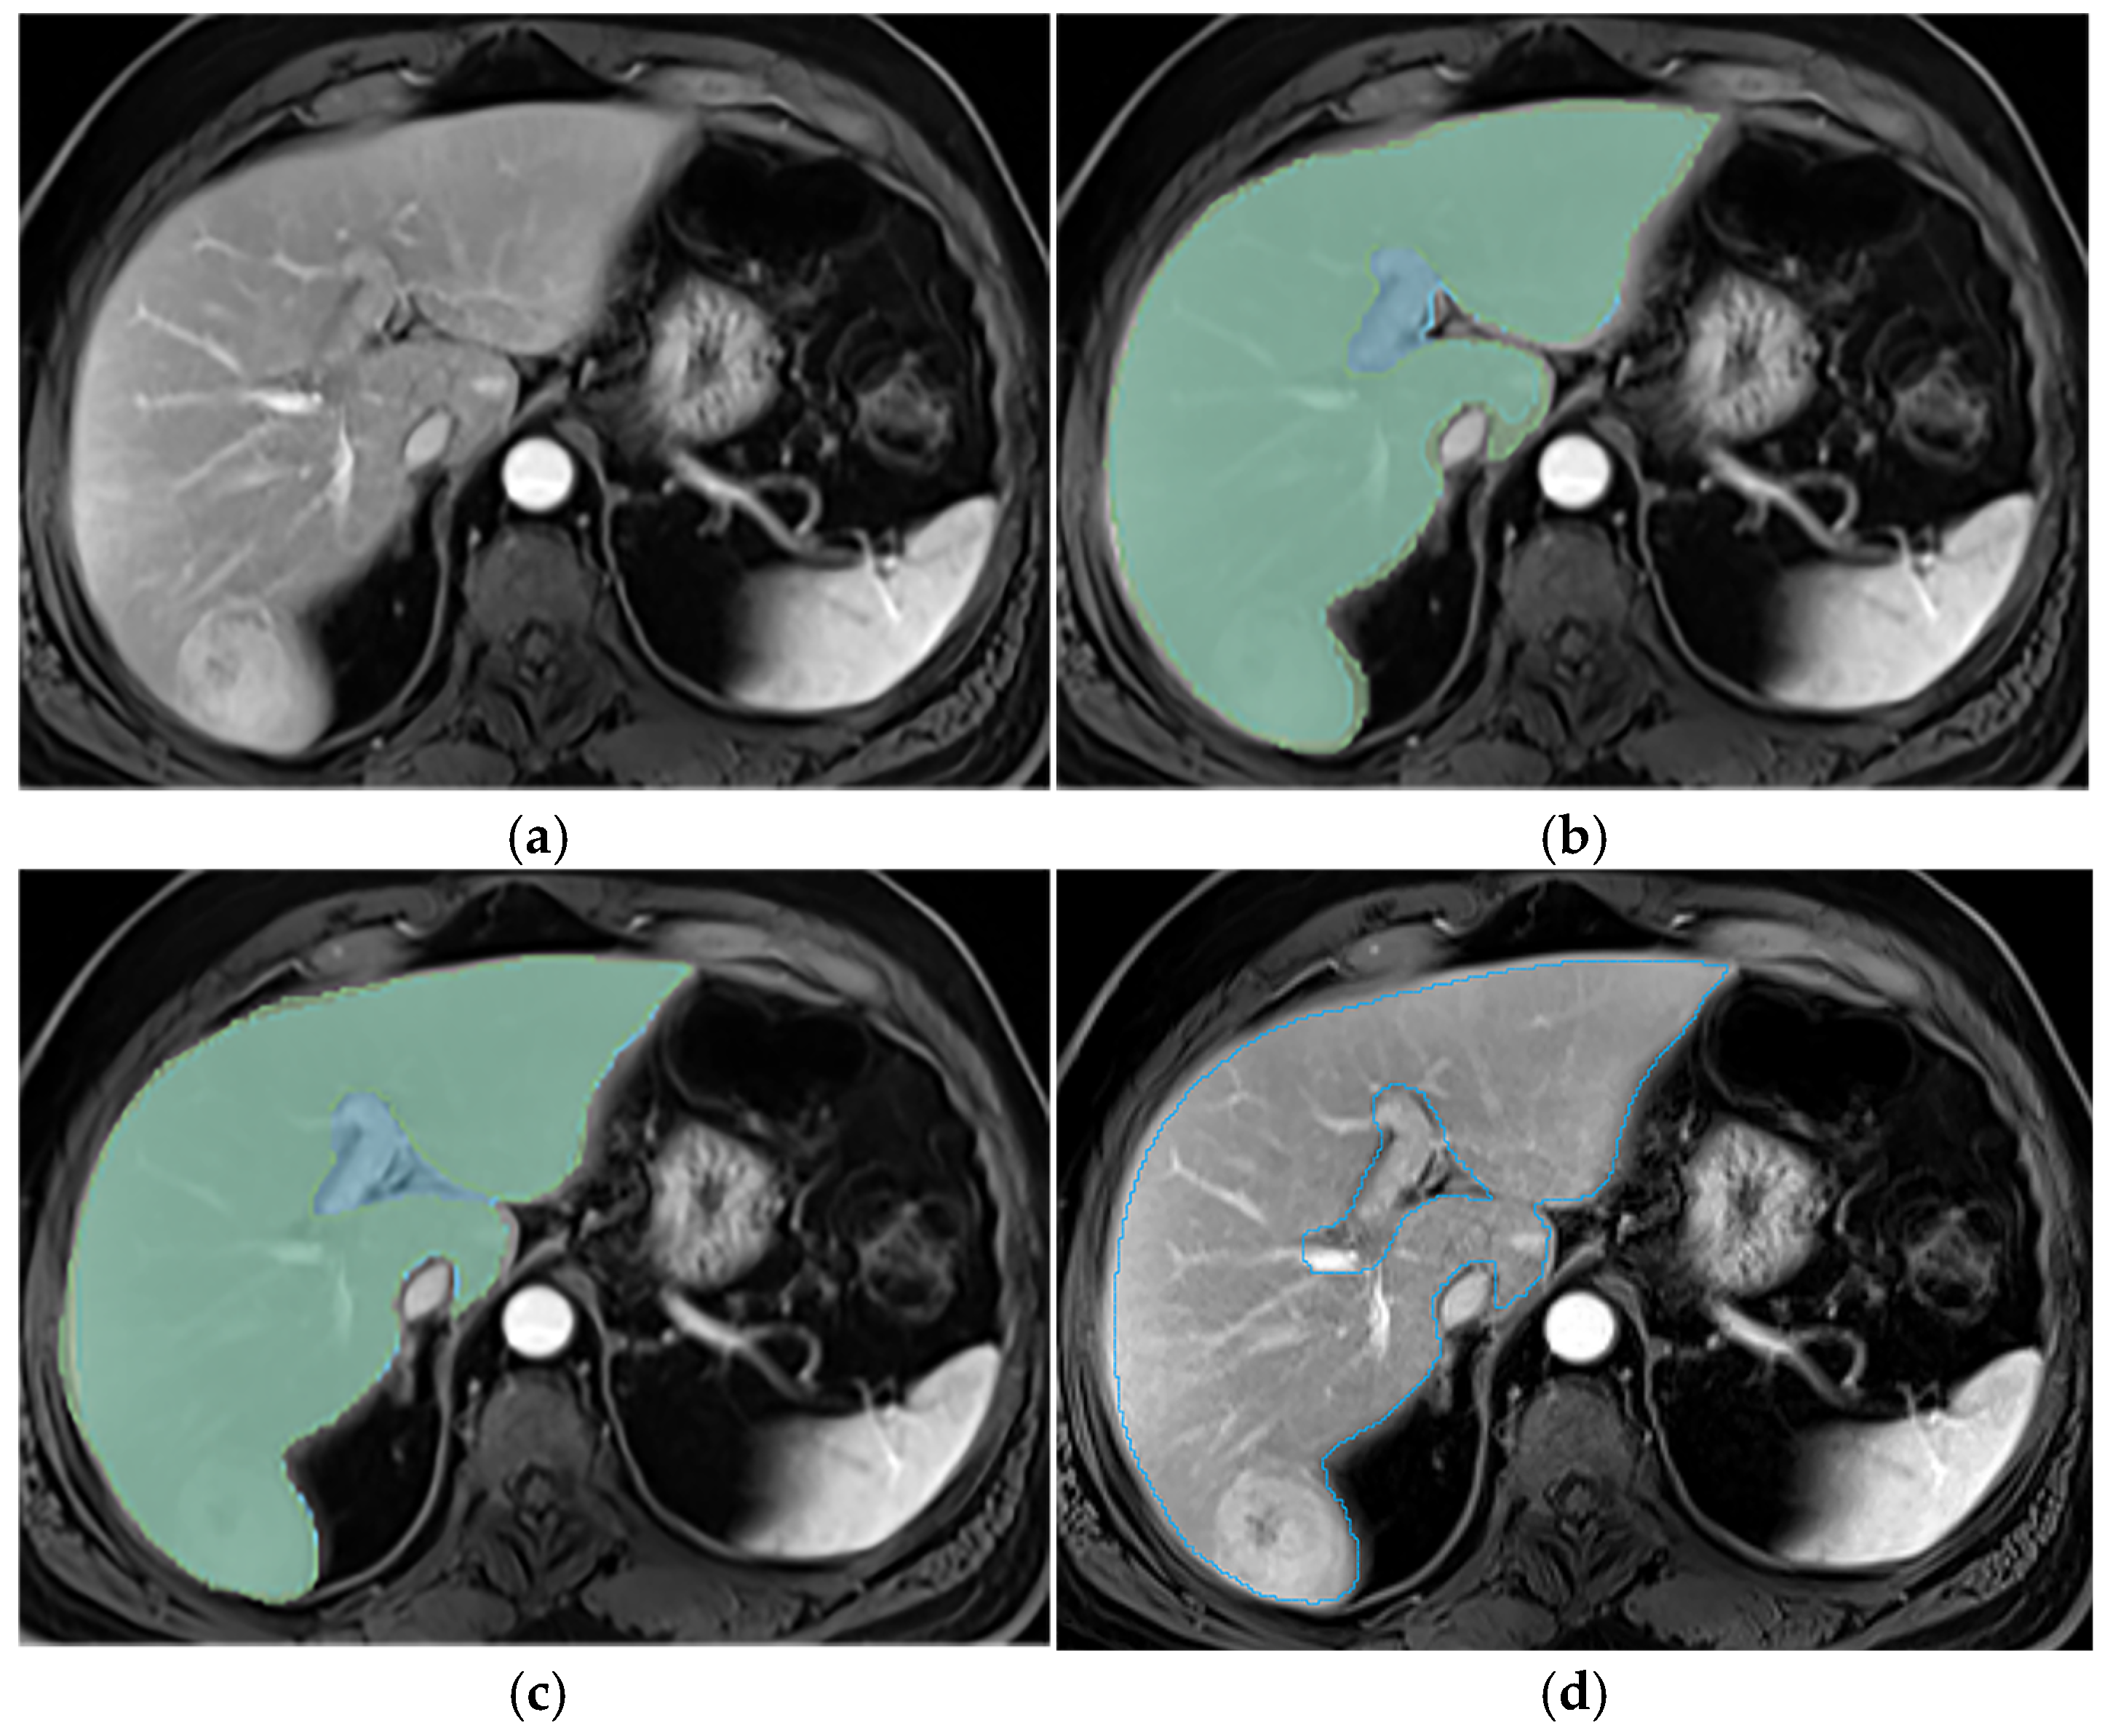

Appendix A.2. Hepatic Hilum Segmentation

Appendix A.3. Vascular Segmentation

Appendix A.4. Ligaments Segmentation

Appendix A.5. Multi-Part Liver Parenchyma

Appendix A.6. Presence of Respiratory Artifacts

Appendix A.7. Ascites